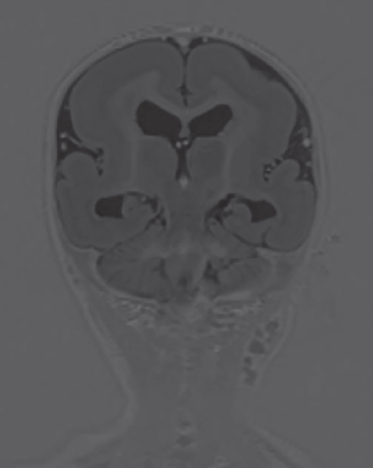

La resonancia magnética cerebral permitió reconocer un engrosamiento difuso de la corteza cerebral de forma bilateral con disminución de la superficie giral suprayacente, así como apariencia lisa de ambos hemisferios (figura 3), además se asoció con la presencia de heterotopia en banda hiperintensa en T1 e hipointensa en T2 (figura 4), así como disminución generalizada del grosor del cuerpo calloso y de ambos hipocampos (figura 5). Mediante este estudio se brindó el diagnóstico de lisencefalia de tipo 1 con heterotopia en banda del grupo IIB.

Figura 5 Corte coronal de la secuencia ponderada en inversión-recuperación que muestra disminución generalizada del grosor del cuerpo calloso y de ambos hipocampos